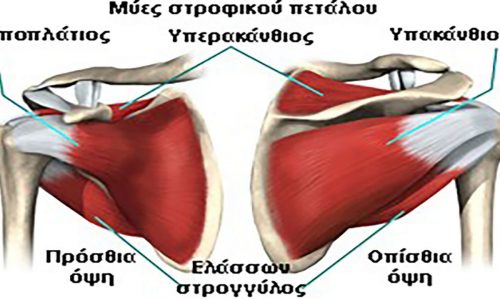

Το στροφικό πέταλο αποτελείται από τους τένοντες τεσσάρων μυών της περιοχής του ώμου(υπερακάνθιο, υπακάνθιο, υποπλάτιο και ελάσσονα στρογγύλο). Είναι υπεύθυνο για την απαγωγή(πλάγια ανύψωση) και τις στροφικές κινήσεις του άνω άκρου. Διατηρεί ταυτόχρονα τη σταθερότητα στην άρθρωση του ώμου, ισορροπώντας αντίθετες δυνάμεις.